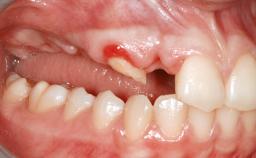

A 46-year-old woman was referred for treatment whose main complaints were mobility of her fixed partial dentures (right maxilla and left mandible) and periodontal bleeding during function. She also reported having taken systemic antibiotics to treat recurrent swelling in the area of the upper left molars. The patient had not seen a dentist for at least 2 years. She did not smoke and had no history of major systemic disease other than two minor orthopedic procedures some years back. The first-visit examination revealed poor plaque control, tooth mobility, periodontal disease, and a residual dentition widely associated with deep periodontal pockets.